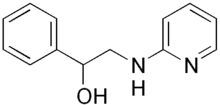

| Formula | C13H14N2O |

| Molar mass | 214.268 g·mol−1 |

Fenyramidol (INN) or phenyramidol (BAN, USAN), trade name Cabral, is a pharmaceutical drug which acts as a muscle relaxant.[1]